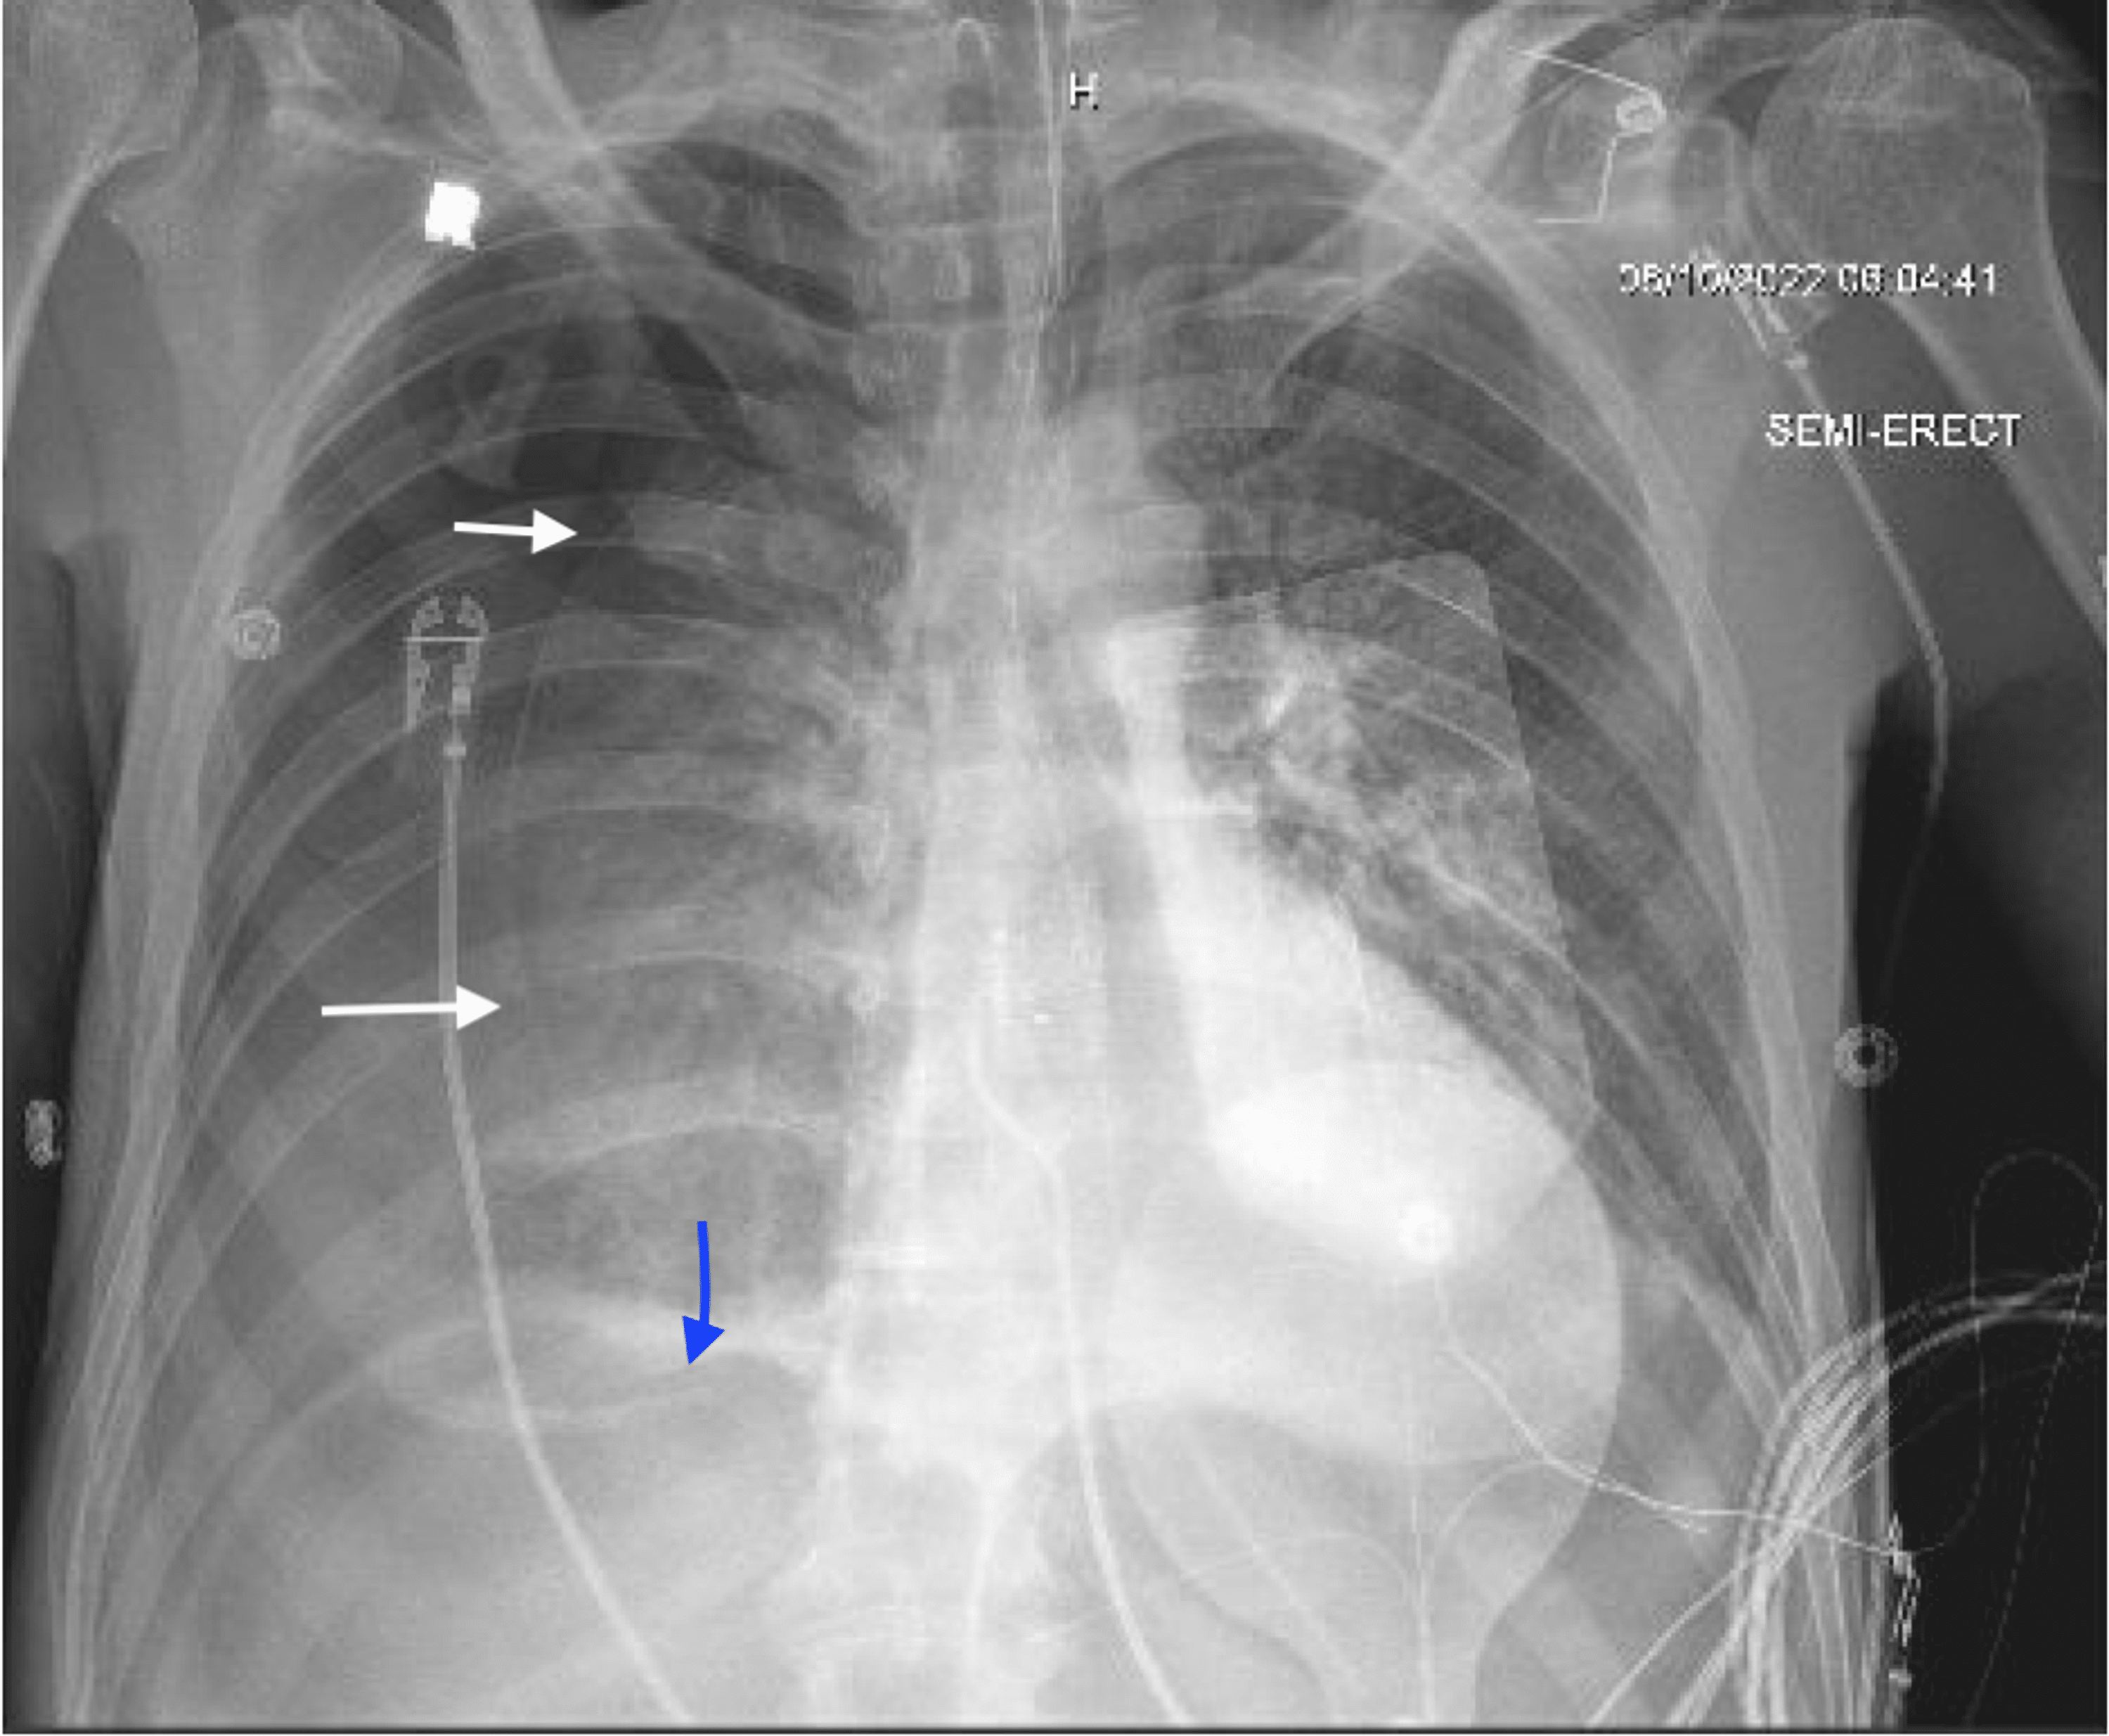

Rare and unexpected complication after a malpositioned nasogastric tube Complications After Ng Tube Removal nasogastric tube syndrome (ngts) induced by a nasointestinal ileus tube is an uncommon but potentially life. Removing an ng tube incorrectly can cause serious complications, such as damage to the airway, which. after tube removal, continue to monitor the client for signs of gastrointestinal (gi) dysfunction, including nausea, vomiting,. common mistakes when removing an ng tube. . Complications After Ng Tube Removal.

Rare and unexpected complication after a malpositioned nasogastric tube Complications After Ng Tube Removal common mistakes when removing an ng tube. Removing an ng tube incorrectly can cause serious complications, such as damage to the airway, which. the most common complications related to the placement of nasogastric tubes are discomfort, sinusitis, or epistaxis, all of which. nasogastric tube syndrome (ngts) induced by a nasointestinal ileus tube is an uncommon but potentially. Complications After Ng Tube Removal.